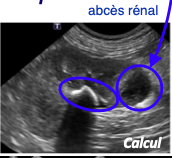

DX? (reins)

calcul + abcès rénal

*on voit bien l’artéfact du cône d’ombre distalement au calcul